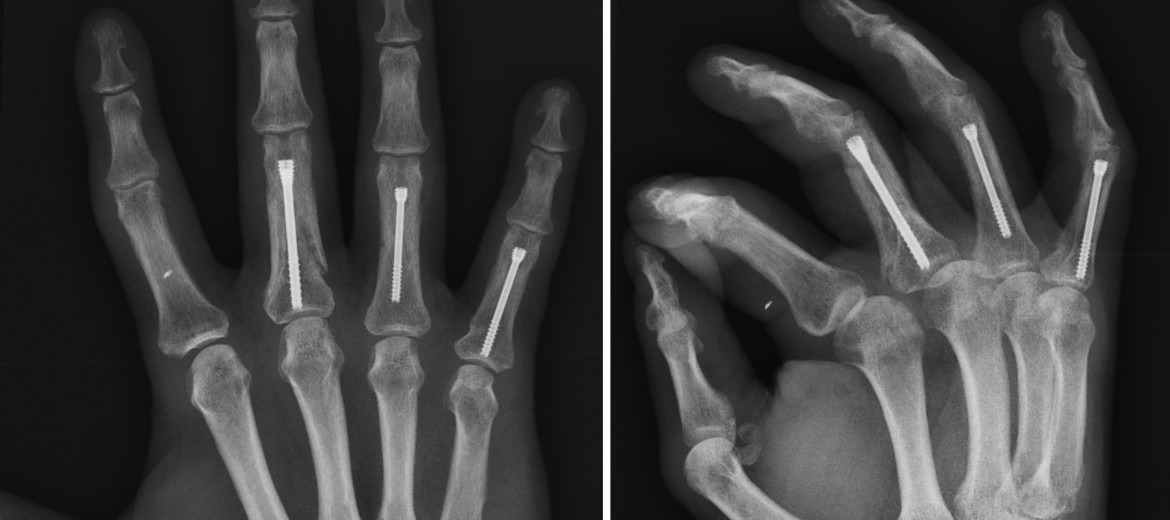

- 폐쇄 정복(Closed reduction): 변위 교정 후 깁스·스플린트 고정.

- 개방적 정복 및 내고정(ORIF): 파편이 많거나 관절 간격이 넓을 때 핀·스크루·플레이트 사용.

- 외고정(External fixator): 심한 연부 조직 손상 동반 시 임시 고정.